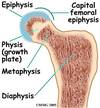

Slipped Capital Femoral Ephysis (SCFE)

- Epiphysis (growth plate) of the femoral head may slip away from the femoral neck due to a weakened epiphyseal plate

- Causes: acute trauma or repetitive microtrauma with shear stress; gradual slippage with associated hip pain that may refer to the knee; antalgic gait

- SCFE usually occurs in: EMERGENCY

◦children between 10- 16 years old*

◦Overweight

◦Boys > girls

◦African Americans > Caucasian

- Classified 2 types: stable and unstable (unstable-unable to weight bear, stable-can walk with crutches, 90%)

- An emergency situation

SCFE Treatment

-Common treatment: “in-situ fixation.”

◦the bone is held in place with a single central screw

◦keeps the femur from slipping and closes the growth plate

◦Good results with few complications

◦Prophylactic bilateral surgical intervention - sometimes

Conservative treatment (NWB) ~ poorer outcomes

*slippage disrupts growth bc disrupts growth plate

*orthopeds will usually choose surgery, if not will go to PT for conservative measures